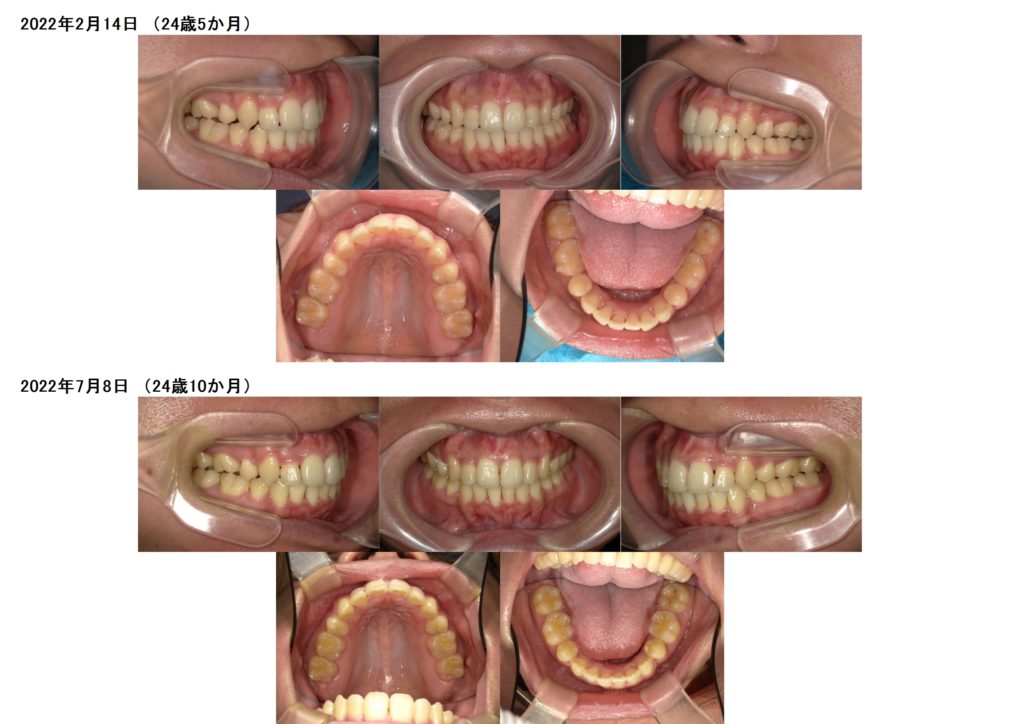

治療前、治療後の口腔内写真です。

お口元も引っ込み、ガタガタ歯並びも治りました。

横顔もとっても変わりましたよ☆

今は、リテーナーを使用し保定期間中です。

その保定期間もとっても大切な期間になります。

リテーナーをしっかり使用しないと歯の乱れの原因となりますので、しっかり引き続き使用していきましょう☺